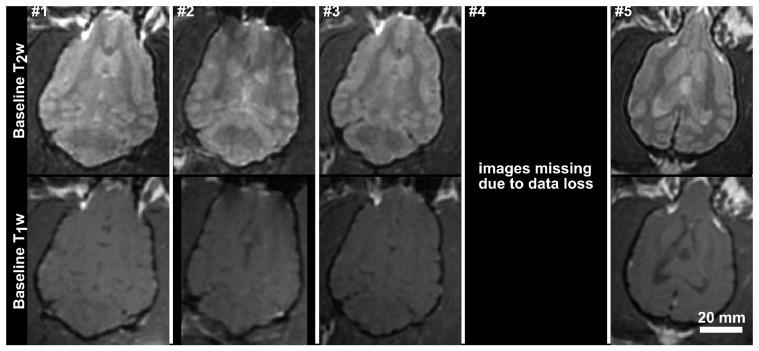

Ultrasound-mediated opening of the Blood-Brain Barrier(BBB) has shown exciting potential for the treatment of Alzheimer's disease(AD). Studies in transgenic mouse models have shown that this approach can reduce plaque pathology and improve spatial memory. Before clinical translation can occur the safety of the method needs to be tested in a larger brain that allows lower frequencies be used to treat larger tissue volumes, simulating clinical situations. Here we investigate the safety of opening the BBB in half of the brain in a large aged animal model with naturally occurring amyloid deposits. Aged dogs naturally accumulate plaques and show associated cognitive declines. Low-frequency ultrasound was used to open the BBB unilaterally in aged beagles (9-11yrs, n=10) in accordance with institutionally approved protocols. Animals received either a single treatment or four weekly treatments. Magnetic resonance imaging(MRI) was used to guide the treatments and assess the tissue effects. The animals underwent neurological testing during treatment follow-up, and a follow-up MRI exam 1 week following the final treatment. The permeability of the BBB was successfully increased in all animals (mean enhancement: 19±11% relative to untreated hemisphere). There was a single adverse event in the chronic treatment group that resolved within 24 hrs. Follow-up MRI showed the BBB to be intact with no evidence of tissue damage in all animals. Histological analysis showed comparable levels of microhemorrhage between the treated and control hemispheres in the prefrontal cortex (single/repeat treatment: 1.0±1.4 vs 0.4±0.5/5.2±1.8 vs. 4.0±2.0). No significant differences were observed in beta-amyloid load (single/repeat: p=0.31/p=0.98) although 3/5 animals in each group showed lower Aβ loads in the treated hemisphere. Whole-hemisphere opening of the BBB was well tolerated in the aged large animal brain. The treatment volumes and frequencies used are clinically relevant and indicate safety for clinical translation. Further study is warranted to determine if FUS has positive effects on naturally occurring amyloid pathology.